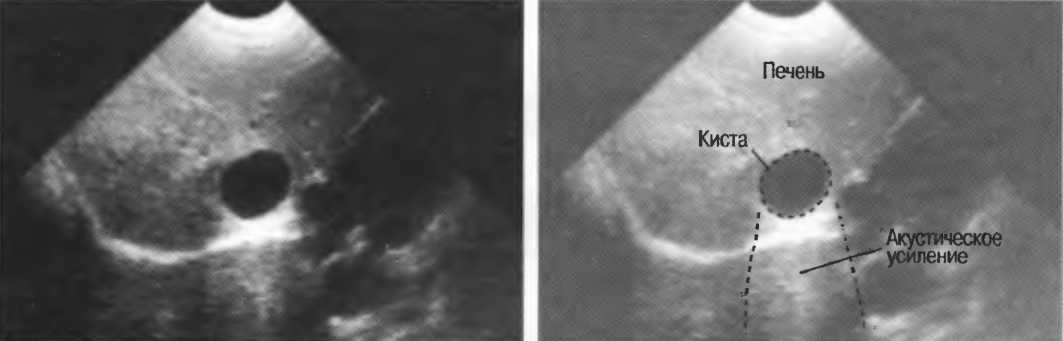

Кисты

Киста, как правило, визуализируется в виде анэхогенной зоны, при этом структуры, расположенные за кистой, обычно усилены: полость кисты анэхогенна, поскольку в ней нет структур с различным акустическим сопротивлением. В результате того что жидкость не поглощает ультразвук в такой же степени, что и ткань, эхо-сигналы от расположенных позади кисты структур гиперкомпенсированы сканером и выглядят усиленными — появляется эффект усиления задней стенки (рис. 14а,б).

Киста определяется в виде анэхогенной зоны с усилением по задней стенке. Если в кисте есть внутренние зхоструктуры, то они могут быть реальными или являться артефактами.

Рис. 14а. Заполненная жидкостью киста: полость кисты анзхогенна, имеется усиление задней стенки.

Структура, наподобие содержащей чистую жидкость кисты, визуализируется как анэхогенная зона. Стенки кисты отражают ультразвуковые сигналы под углом, и информация не поступает назад в трансдьюсер. В результате этого появляются боковые тени, но сзади кисты имеется усиление эхосигналов (усиление задней стенки) (рис. 15).

Рис. 15а. Киста печени: жидкость внутри чистая, анэхогенная. Стенки кисты отражают ультразвук под углом от датчика, вызывая появление боковых теней.